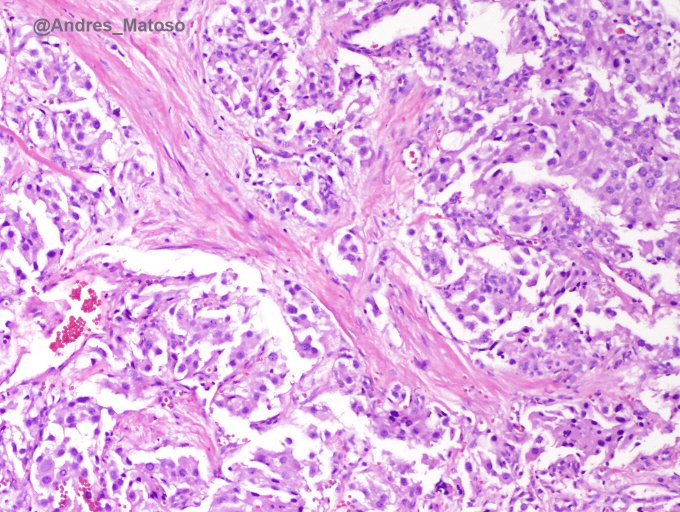

Andres Matoso

@Andres_Matoso

Not every tumor in the detrusor is urothelial carcinoma. Here is a nice example of paraganglioma. Look SDH! #GUpath #pathology #urology pic.twitter.com/sn6bpdkD3T